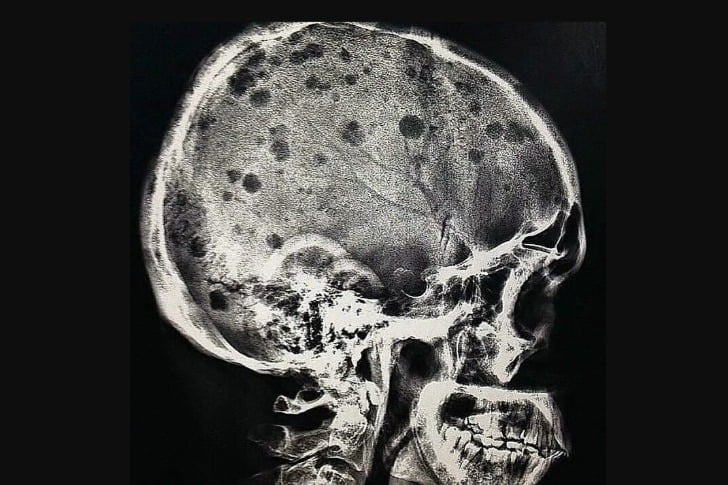

#32 Un patient atteint de myélome multiple

L’aspect radiographique classique du myélome multiple est celui de lésions multiples, petites, bien circonscrites, lytiques, « à l’emporte-pièce » et rondes au niveau du crâne, de la colonne vertébrale et du bassin. Le motif des lésions radiotransparentes lytiques ou « à l’emporte-pièce » sur le crâne a été décrit comme ressemblant à des gouttes de pluie frappant une surface et éclaboussant.